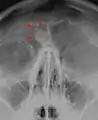

Osteoma of the frontal sinus seen on x-ray